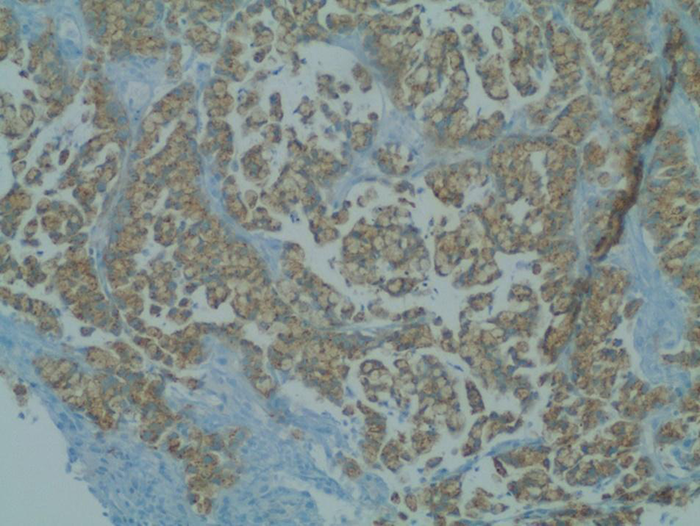

Fourteen lymph nodes were harvested, and all were negative for metastasis (Stage T4N0M0). The tumor was positive for neuron specific enolase (NSE) (Figure 2) and synaptophysin (Figure 3), but chromogranin A and CD56 negative. Histological examination of the appendix was normal (Figure 4).

Figure 3. Primary goblet cell carcinoid tumor staining positive for synaptophysin